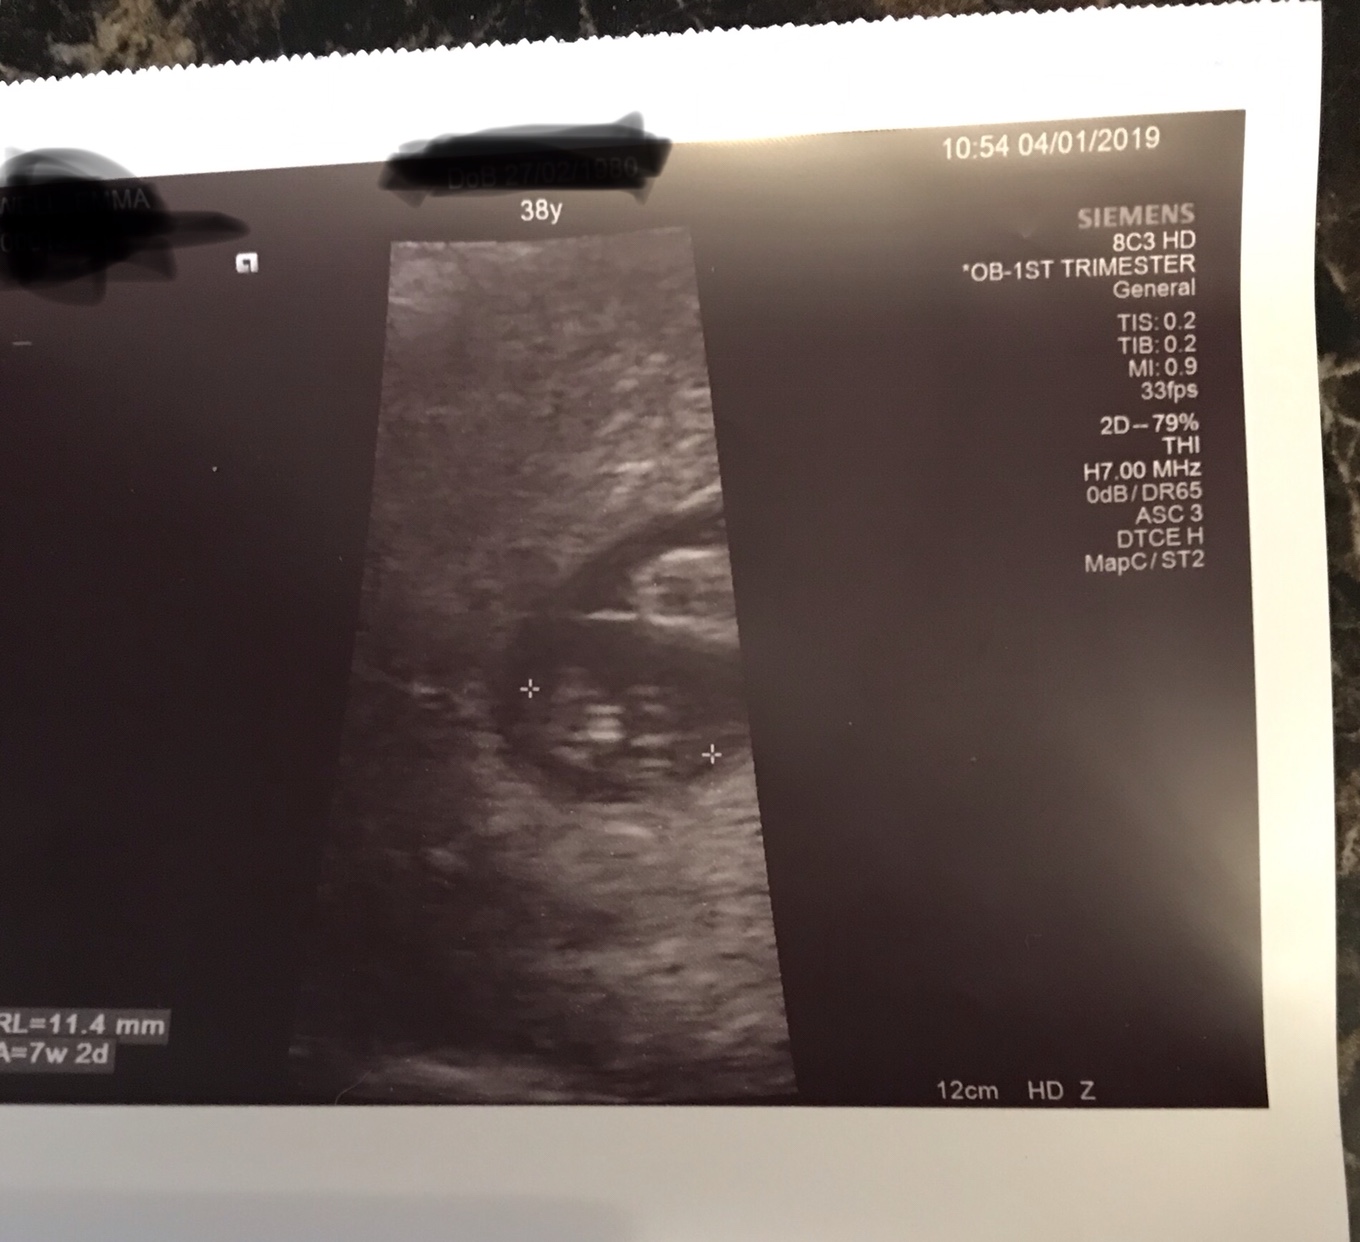

yolk sac size chart Diagnostic ultrasound in the first trimester of pregnancy

Diagnostic Ultrasound In The First Trimester Of Pregnancy | GLOWM

Diagnostic Ultrasound in the First Trimester of Pregnancy | GLOWM www.glowm.com

pregnancy ultrasound trimester yolk early sacs enlarged loss diagnostic mm section